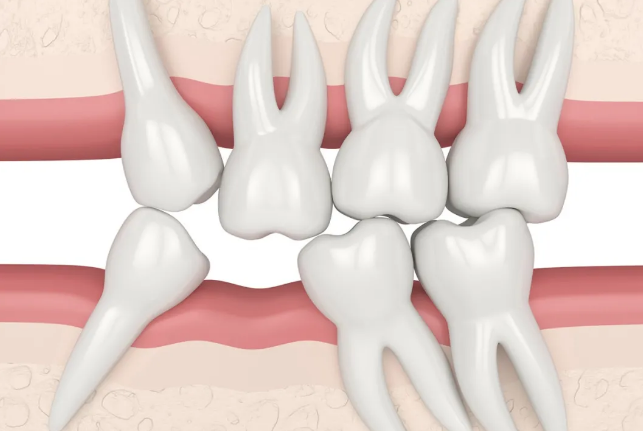

一颗牙齿缺失后,对合的牙齿会逐渐伸长“冒”出来,相邻的两颗牙齿会因为没有了长期依靠的小伙伴,开始慢慢向缺牙空位间倾斜,时间长了,就会造成周围邻牙的松动,从而使全口牙齿的正常功能都遭受严重破坏。

我们正常的牙齿与牙齿之间,排列得十分紧密,一旦邻近的牙齿发生位移,那么牙齿与牙齿之间就会出现缝隙,吃饭时,食物就很容易塞嵌到牙缝里,腐质变臭,从而引起口臭、龋齿、牙周病等问题。》》》推荐阅读:缺了一颗牙,必须要做种植牙吗?

小编在上面危害中提及到,牙齿缺失会造成食物嵌塞,而食物嵌塞到牙缝里,很不容易清洁干净,牙缝大的朋友应该深有体会,每次都是牙签、牙线齐上阵。食物残渣加上细菌,长时间堆积在我们的牙周,就会导致龋齿的出现,还有黄黄的牙结石,威胁我们的牙齿稳固和牙周健康,最终,“三缺一”变成了“一缺三”。